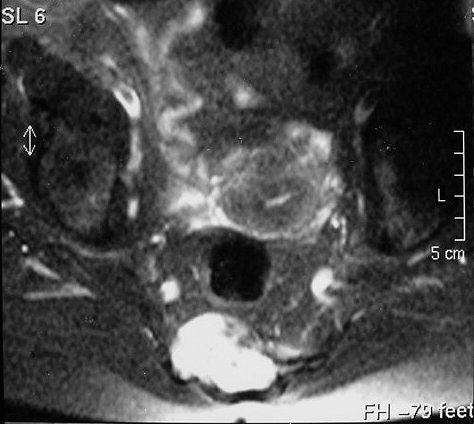

Внутричерепная хордома.

http://pubs.rsna.org/doi/full/10.1148/rg.234025176